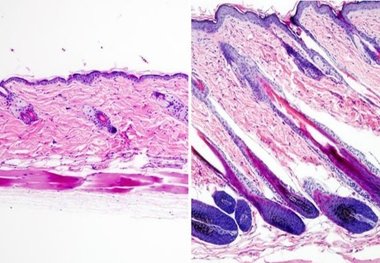

طاسی سر با روغن چوب صندل درمان می شود

محققان ادعا می کنند مالیدن روغن چوب صندل بر روی پوست فرق سر موجب تحریک رشد مو در مدت ۶ روز می شود.